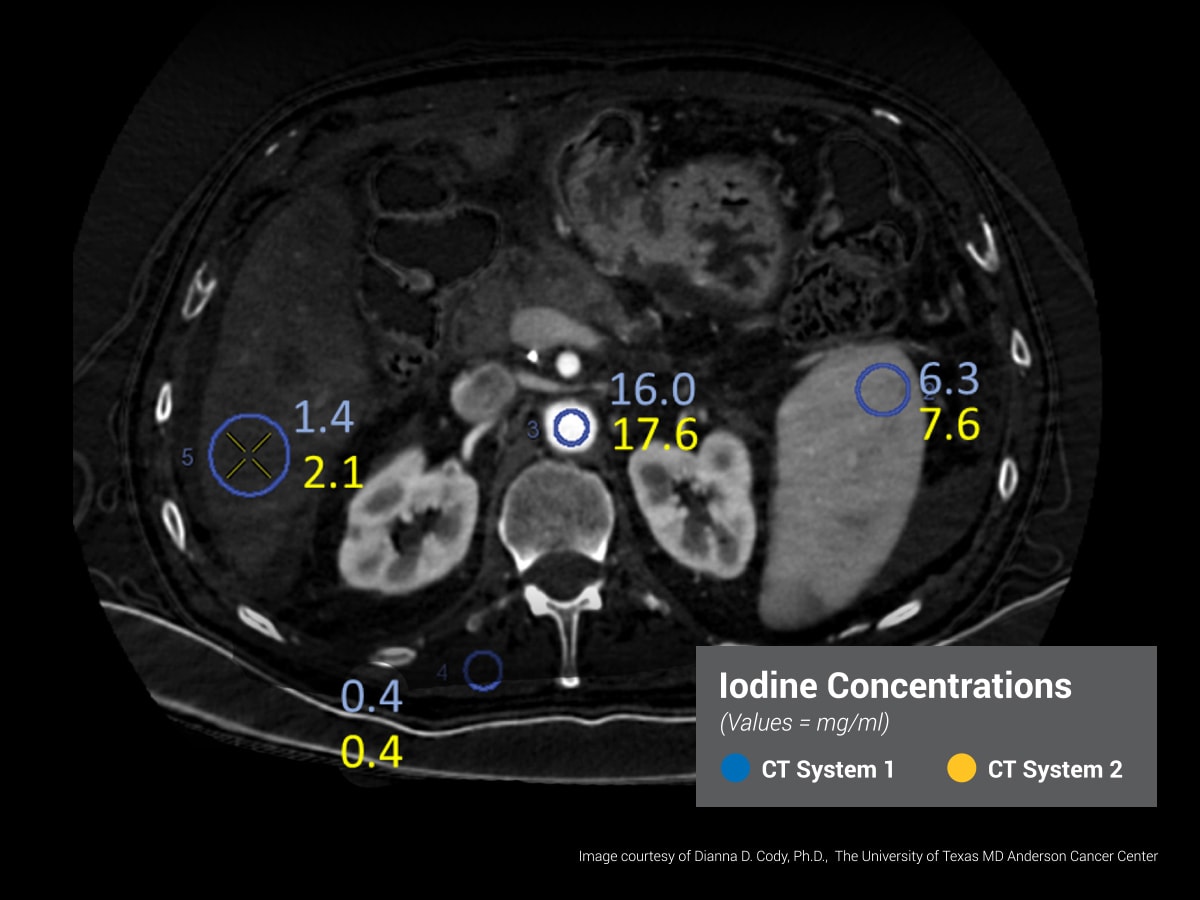

Dễ dàng kiểm tra khả năng phân biệt vật chất bằng cách sử dụng các thanh rắn mô phỏng các chất như iod, canxi, máu, mô mỡ và nhiều chất khác. Các thanh đánh dấu được cấp bằng sáng chế cho phép phân tích tự động, giúp quy trình này trở nên nhanh chóng và hiệu quả hơn.

Kiểm tra hiệu quả của các phác đồ lâm sàng trong phân tích đa năng lượng và so sánh tính ổn định, độ nhất quán giữa các máy chụp khác nhau.